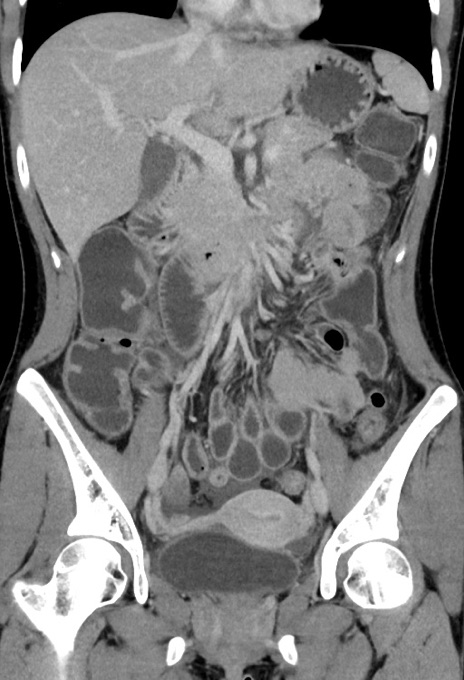

症例17(冠状断像)

【症例】20歳代女性

【主訴】嘔吐、下腹部痛

【現病歴】昨日夕食後に嘔吐し下腹部痛が出現。本日になっても嘔吐持続し改善しないため来院。

【身体所見】意識清明、BT 37.2℃、BP 108/67mmHg、腹部:平坦、やや硬、下腹部正中から右にかけて圧痛あり、反跳痛軽度あり、tapping pain(+)。

【データ】WBC 13600、CRP 14.94